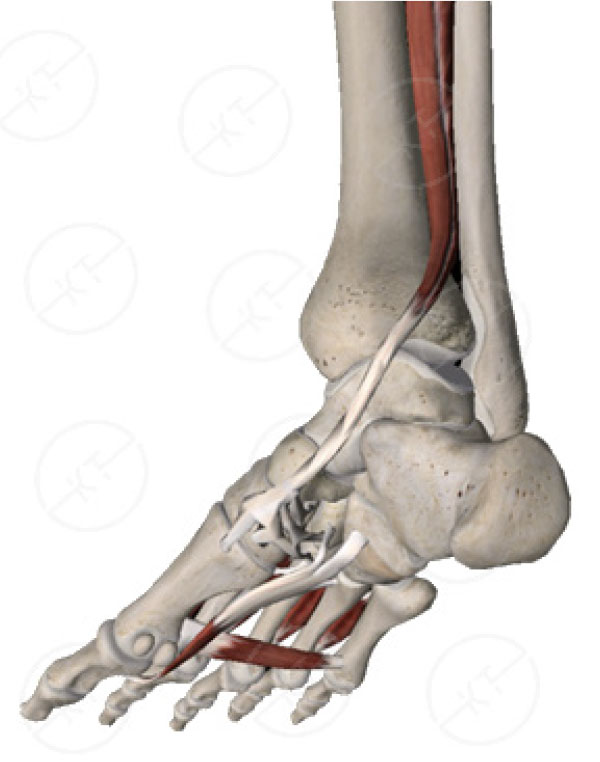

Posterior tibial store tendonitis inserts